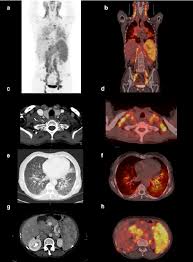

Advanced Technology for Accurate Imaging

One of the key strengths of the Best FDG PET CT Scan in HauzKhas is the use of advanced PET CT scanners that provide high-resolution images and precise metabolic mapping. Modern technology allows doctors to identify even small lesions with greater confidence.

Clear and detailed imaging

Faster and smoother scan procedures

Accurate disease localization

Improved treatment planning